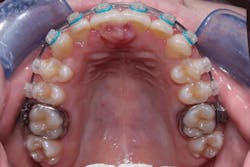

Figure 1: Clinical view of peripheral ossifying fibroma

Courtesy of Drs. Jordan McHone and David Klingman

These fibromas are seen in soft tissues of the gingiva. The incisor-cuspid area is often favored, extending into the interdental papilla areas of the maxillary arch. The growths present as either sessile or pedunculated. They tend to occur on the gingiva, predominately in young adults and women. Histological examination reveals cellular fibroblasts and connective tissue strands with islands of calcified material and cementoid-like material (odontogenic).

Bharathi et al., in a recent article, presented descriptions of four cases of gingival overgrowth. The authors state that the cementoid material found in a POF may be due to the presence of epithelial cell rests of Malassez promoting odontogenic epithelium (see Figures 1, 2). Ashok et al. (2016) make the point that some authors believe that the cells ultimately lead to the formation of bone by metaplasia.